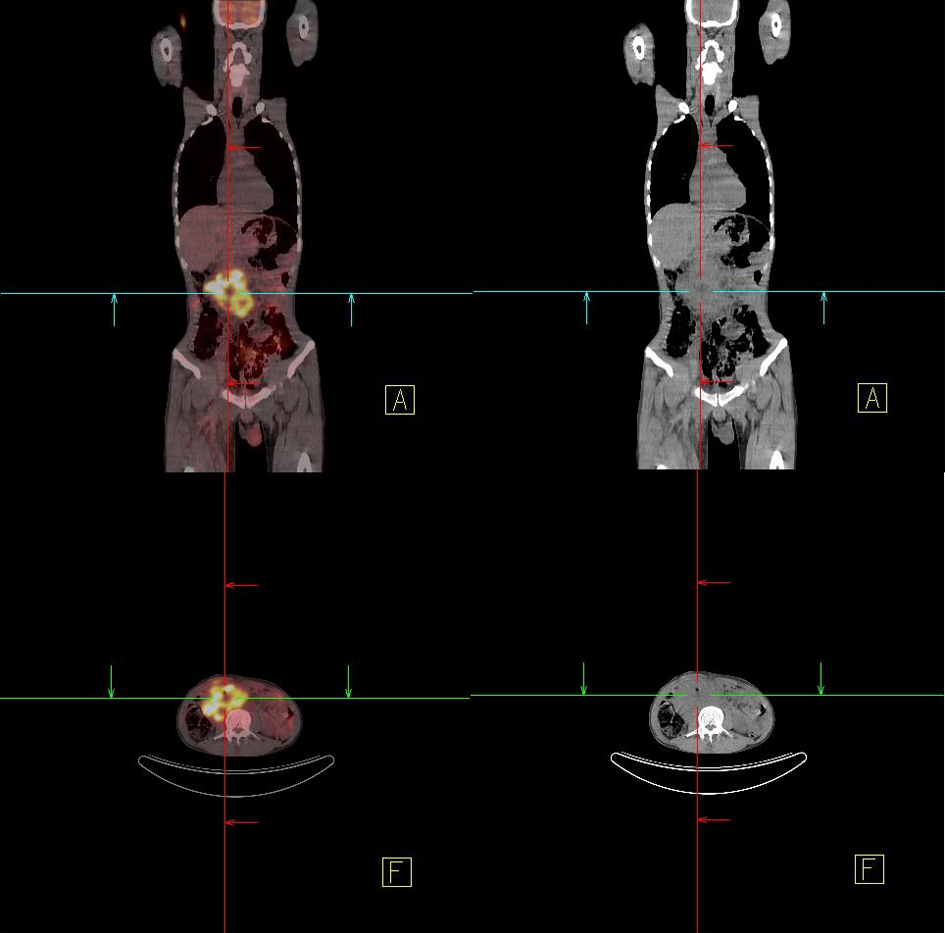

A 34-year-old male patient was admitted with complaints of upper-gastrointestinal bleeding and vomiting. Physical examination was normal except for an epigastric palpable mass. Complete blood count gave hemoglobin 8 gr/dL and hemarocrit 25%, and LDH was 426 U/L. In endoscopy, a polypoid mass which obstructing 80% of the lumen was seen in the second part of duodenum. In computer tomography, a mass 10 x 9 x 7 cm in size was detected in duodenum. In PET-CT, a tumor from retroperitoneal site invading to duodenum was showed (Fig. 3). There was no distant metastasis. Because of upper-gastrointestinal bleeding and duodenal obstruction, palliative antecolic gastroenterostomy was performed. Since the tumor was locally-advanced stage, partial resection was applied. On microscopic examination, generally solid and some glandular architectures including zones of eosinophilic coagulative necrosis were observed in the tumor with large polygonal shaped cells showing ill-defined cytoplasmic borders and cytoplasmic vacuolation similar to lymphoblast or signet ring cells, on the other hand Immunohistochemical staining showed patchy placental alkaline phosphatase (PLAP) reactivity (Fig. 4) and focal weak alpha-fetoprotein (AFP) positivity in the tumor cells reminiscent of an embryonal carcinoma with a yolk sac tumor component. In germ cell tumors, the positive of PLAP and AFP are specific. In the result of post-operative pathology, germ cell tumor, especially embryonal cell carcinoma type was reported. Tumor markers of the patient were as follows; increased AFP (321 IU/mL), and normal HCG (< 1 mIU/mL). After palliative operation, 6 cycles BEP (Bleomycin, Etoposit and Cisplatin) were given as primary chemotherapy. Following the chemotherapy, high AFP level decreased and tumoral mass was shown to be disappeared by (PET-CT) in the follow-up control. After completion of his treatment, the patient followed -up in remission for 6 months.

![]() Click for large image | Figure 3. In PET-CT, a retroperitoneal mass. |